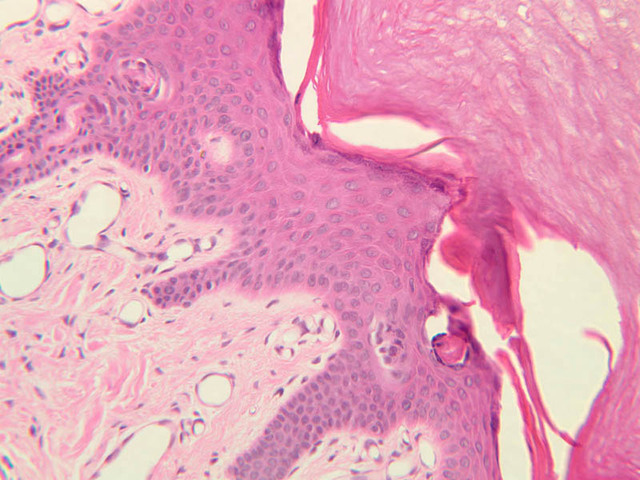

Examine slide A-50 (fingertip, H&E [2.5x, 10x-labeled, 20x, 40x-labeled] [20x, 40x] [10x, 20x, 40x] [20x, 20x, 40x]), and study the morphology of five layers of thick skin. The deepest part of the epidermis comprises the stratum basale which provides the cells required for continual renewal of the epidermis. This stratum is composed of a single layer of columnar or cuboidal epithelial cells attached to the basement membrane.

Superficial to the stratum basale is a multi-cellular layer known as the stratum spinosum, consisting of polyhedral cells that have a "prickly" or spiny appearance (A-50, langerhans cells [10x, 20x-labeled, 40x-labeled] [40x, 40x-labeled, 40x, 40x-labeled]; A- 48, abdominal skin, H&E [10x, 20x, 40x] [40x, 40x, 40x, 40x]). The spiny cells are separated by intercellular spaces that are bridged at numerous points by cytoplasmic processes, which in turn are bound together by desmosomes. The cytoplasmic processes projecting on all sides from the cells give them the spiny appearance to which the name refers. These are best seen under high power. Langerhans cells can also be found in this layer.

Superficial to the stratum spinosum is a layer of flattened cells with coarse, deeply-stained cytoplasmic granules, the stratum granulosum (slide A-50 [40x] [40x, 40x] [40x-labeled, 40x, 40x]). These are keratohyalin granules and evidently represent a stage in the keratinization of the epidermal cells. Note that the nuclei of the more superficial granular cells appear dense and pyknotic, foreshadowing their disintegration and the resultant death of the cells.

The stratum lucidum is often considered to be a subdivision of the stratum corneum. This layer is evident only in thick (glaborous) skin. It appears as a clear band beneath the stratum corneum. Cells of the stratum lucidum are well advanced in the process of keratinization. Consequently, the nucleus and many of the cytoplasmic organelles become disrupted and disappear as the cells become filled with the intracellular protein keratin. In many specimens, there is a separation artifact at this point. The outermost layer of the epidermis is called the stratum corneum and is composed of fully cornified (keratinized) remnants of epithelial cells ([40x]). It has a basketweave appearance. The close union of the resulting scales with each other, and their content of insoluble protein and extracellular lipids, provides a barrier to diffusion between the body and its external environment.